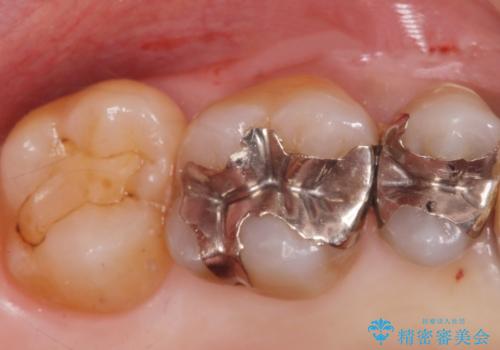

- 前歯(右上2)が黄色いとのことで来院。

レントゲンを撮ったところ前歯の被せ物が不適でした。

根管治療はご希望されなかったので(症状はなし)被せ物のやりかえ、右上2は被せ物の治療を行いました。